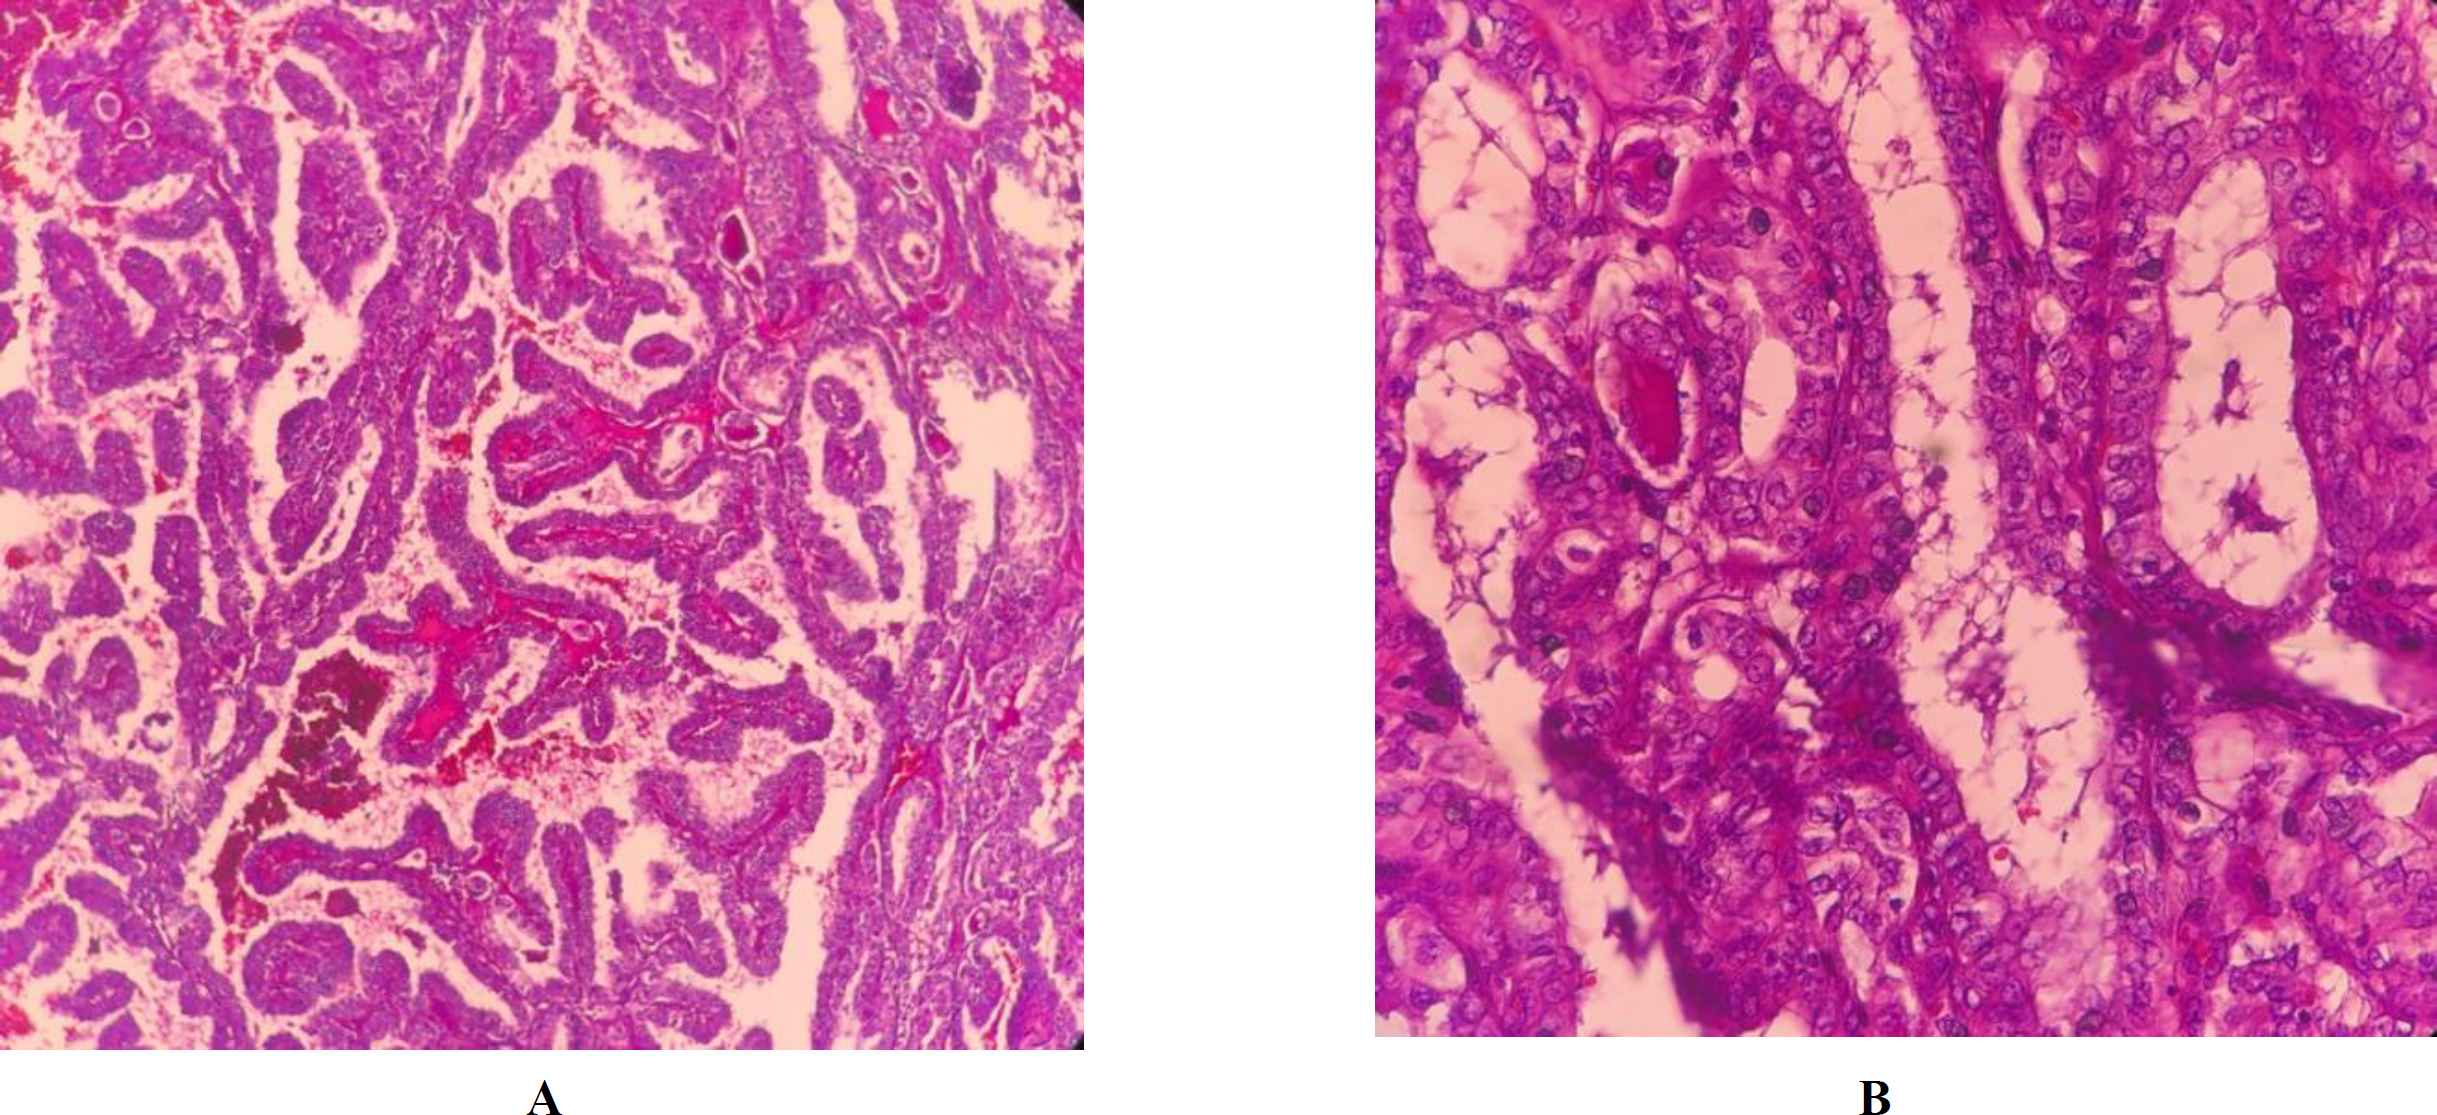

Frozen section examination and permanent sampling slides showed the coexistence of PTC (papillary structure populated by tumoral cells with high N/C ratio, ground glass nuclei with molding, groove and pseudo nuclear inclusion) (Figure 1 A, B) with bilateral MTC (Figure 2 A, B) in the setting of Hashimoto's disease (Figure 3) and MNG .

Fig. 1. A, B.Papillary thyroid carcinoma, (X40 and 400, H&E)